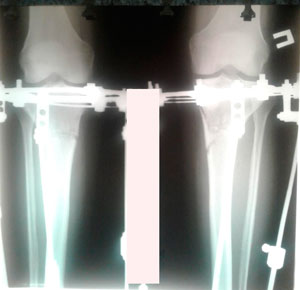

Рентген в 60 дней